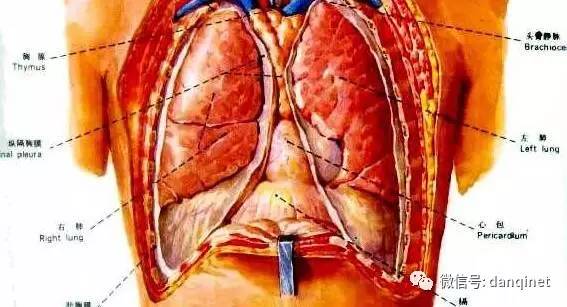

肺癌的临床表现会很多,早期并没有什么特殊症状,仅为一般呼吸系统疾病所共有的症状,如咳嗽、咳痰、痰中带血、低热、胸痛、气闷等,如果不留意,根本不会留意是肺癌,尤其是咳嗽、咳痰为主时.

3咳痰带血_ 如果在平时感冒的时候就会喉咙生痰,并伴有咳痰的现象,有时候也会痰中带血,这说明身体中的炎症非常的严重所引起的,但如果是一旦患上肺癌以后,也会出现咳痰的现象,所以很多人都会认为这是单纯的感冒所引起的,就当做感冒来进行有效的治疗,其实如果是肿瘤

1.持续咳嗽,抗炎治疗无效_ 肺癌的常见症状中就包括了刺激性咳嗽,如果你咳嗽经过治疗后仍未好转,还从有痰变成干咳无痰、咳嗽音调改变、痰中带血,出现这些症状时就要高度警惕肺癌的可能.

肺结核_ 肺结核的主要症状是_ 连续咳嗽、咯痰2周以上或痰中带有血丝.